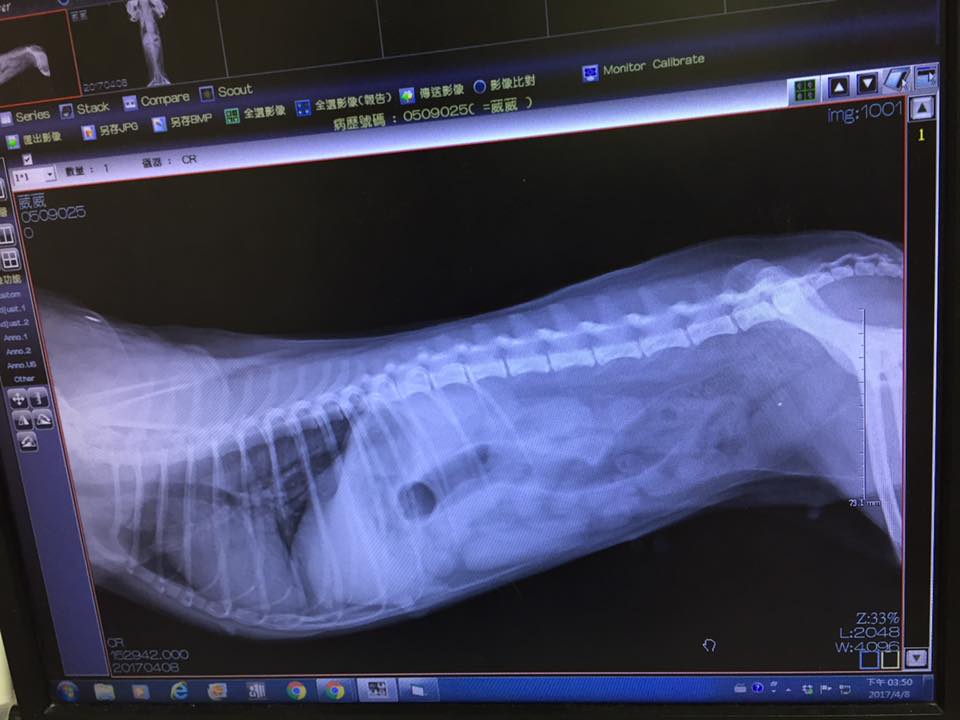

由於葳葳的雙後腿嚴重變形無力,若不開刀治療

未來不久後可能無法行走

於是與醫生討論後,決定替葳葳雙腳開刀

4/6

葳葳劇烈嘔吐後血檢有脫水現象無胰臟炎,x光檢查排除誤食異物,

但脹氣很嚴重此時服藥無法吸收,今天在醫院打抗生素、制酸劑、止吐劑,